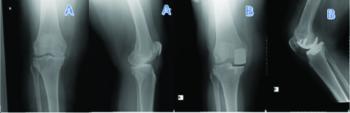

Fixed-Bearing versus Mobile-Bearing Unicondylar Knee Arthroplasty: Comparison...

Comparison of the Results of Two Consecutive Separate Learning Periods in...

Outcome of mobile and fixed unicompartmental knee arthroplasty and risk factors...